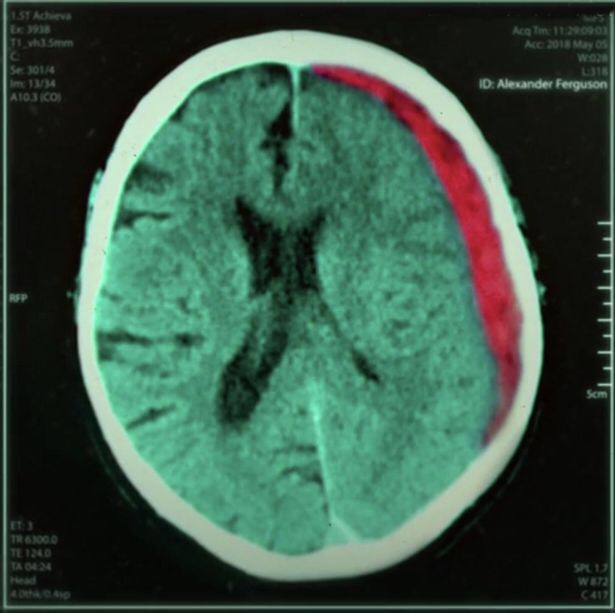

Yesterday myself and my dad watched Sir Alex Ferguson: Never Give In on Amazon prime. It was a really inspiring, heart warming documentary on his life and career. I personally wanted to watch it as he has suffered a brain injury in his later years. But you see from the program he did not let the brain haemorrhage win.